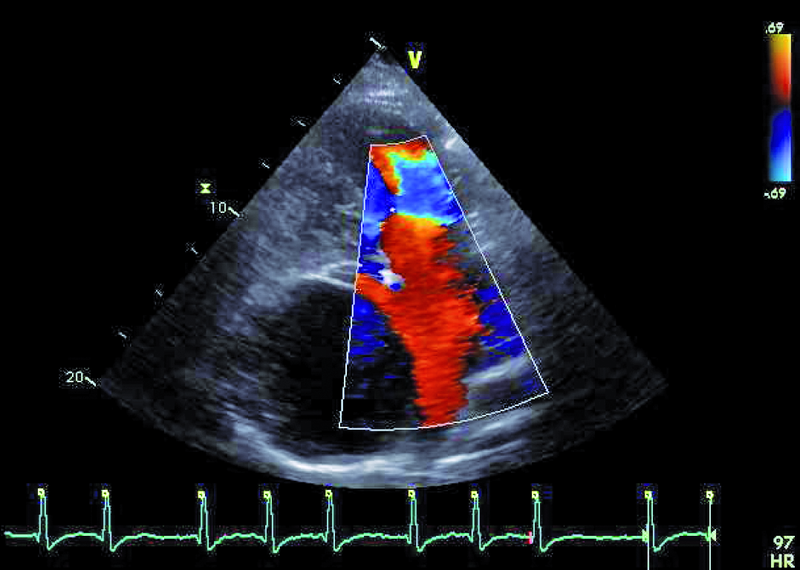

Operację Fontana, będącą rodzajem zabiegu paliatywnego, wykonuje się w celu korekcji zaburzeń hemodynamicznych towarzyszących wspólnej komorze. Celem operacji jest zmniejszenie przeciążenia objętościowego komory, ponieważ otrzymuje ona napływ zarówno z żył płucnych, jak i systemowych. Jest wiele rodzajów serca jednokomorowego. Najczęściej spotyka się zespół z atrezją trójdzielną, niedorozwojem lewej komory, zarośnięciem tętnicy płucnej, dwunapływową komorą lewą, dwuodpływową komorą lewą lub prawą. W podanym przykładzie można wyróżnić dwie zastawki przedsionkowo-komorowe, a więc krew wpływa do wspólnej komory (anatomicznie lewej) zarówno przez ujście trójdzielne, jak i mitralne, co dowodzi obecności komory dwunapływowej (ryc. 1-4). Celem operacji w tym wypadku było nie tylko oddzielenie spływu z żył systemowych, ale także zwiększenie całkowitej objętości krwi płynącej przez łożysko tętnic płucnych. Jak oceniać echokardiograficznie pacjenta po operacji metodą Fontana? Nie dziwi, że wspólna komora jest powiększona (ryc. 1, 2, 5), przerośnięta (ryc. 1, 2) i wykazuje upośledzoną kurczliwość. Jeśli wykształcone są dwie zastawki przedsionkowo-komorowe, należy ocenić każdą z nich, ponieważ fale zwrotne powodowane przez zastawki mogą zwiększać objętość komory i niekorzystnie wpływać na funkcję kurczliwą mięśnia. Niedomykalność zastawek przedsionkowo-komorowych (w podanym przykładzie umiarkowana [ryc. 5]) może także zwiększać ciśnienie w jamie lewego przedsionka, co zmniejsza konieczny dla wytworzonego zespolenia gradient ciśnień: żyła systemowa – tętnica płucna – lewy przedsionek. Wynikiem zmniejszania się gradientu może być narastanie ciśnienia w kanale Fontana (ryc. 1-3), pojawienie się hepatomegalii, przesięków do jam ciała, zespołu enteropatii z hipoproteinemią. Niemal u wszystkich chorych po operacji Fontana obserwuje się poszerzenie światła żyły głównej dolnej ze zwolnieniem przepływu krwi i zjawiskiem samokontrastowania się. Nie zawsze udaje się precyzyjnie uwidocznić morfologię wykonanego zespolenia. W tym wypadku mieliśmy do czynienia z tzw. starym jego rodzajem, polegającym na bezpośrednim połączeniu prawego przedsionka z pniem tętnicy płucnej bezpośrednio (ryc. 6). Metoda taka (Fontana-Linsa) stosowana była w latach 70. i 80. ubiegłego stulecia. W przypadku ciężkiego upośledzenia funkcji kurczliwej wspólnej komory, braku zwężenia w kanale Fontana i wykluczenia istotnych niedomykalności zastawek przedsionkowo-komorowych postępowaniem z wyboru pozostaje zabieg przeszczepienia serca, do którego chory został zakwalifikowany.